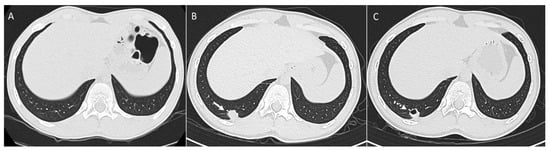

2.1. Parenchymal Metastasis

2.5. Management

7. Role of Chest CT